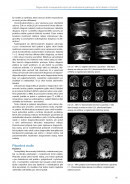

1

2 3

4 5

6 7

8 9

10 11

12 13

14 15